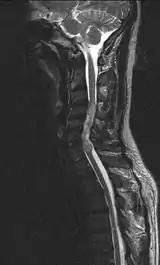

Ependymoma of the cervical spine, completely obscurating the spinal canal

Froin's syndrome – coexistence of xanthochromia, high protein level and marked coagulation of cerebrospinal fluid (CSF). It is caused by meningeal irritation (e.g. during spinal meningitis) and CSF flow blockage by tumour mass or abscess.[1] Stagnation of the CSF within the thecal sac facilitates exudation from the tumour itself and activation of coagulation factors. A clinical test formerly used for evaluation of spinal stenosis is Queckenstedt's maneuver. Nowadays, a magnetic resonance imaging is used for identification of CSF flow obstruction. It often shows the prolongation of T1 and T2 signal in CSF caudal to a level of block.[2] This phenomenon is named after Georges Froin (1874–1932), a French physician who first described it.[3][4]